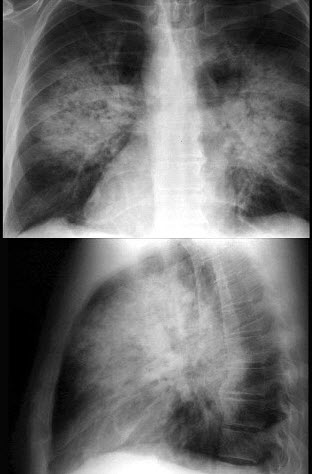

40、单项选择题

男,8岁,胸闷、气急1月余,查体见颈静脉显露,胸片如图,最可能的诊断是()

A.心包积液

73、单项选择题

患者输液过程中突发胸闷、气急、咳痰,胸片如图,最可能的诊断为()

A.矽肺合并感染